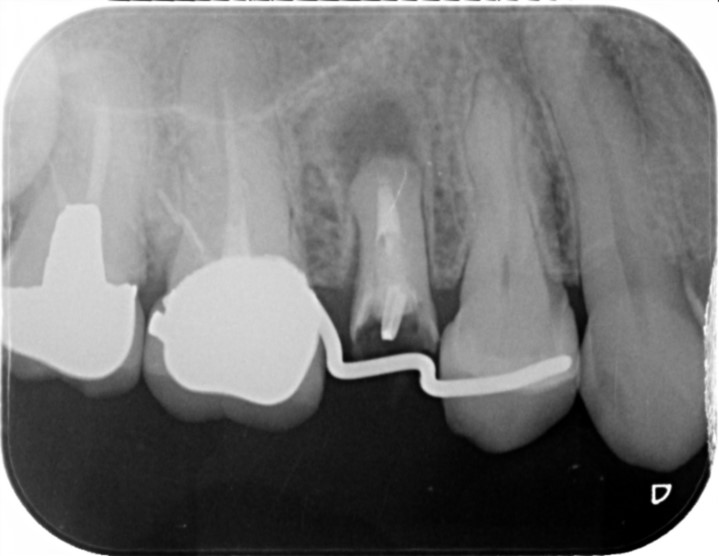

50代男性

画像

R2.7

R5.5

治療部位 左下6,7

費用 約700000円

治療期間 約6ヶ月

痛み、腫れを感じておりレントゲンを撮影、歯が破折している可能性がありました。

被せ物を外しヒビが確認されなければ根管治療で歯を残せる可能性があること、

ヒビがあった場合は抜歯になってしまうと説明しました。

このケースは残せる状態ではなく抜歯という選択になりましたが、できるだけ患者様のご希望に寄り添い、

治療計画をご提案できるよう最善を尽くしております。